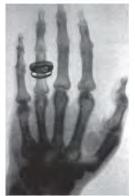

хірургічного втручання, застосувавши

випромінювання (іл. 8). Його використання є

(КТ), яка дозволяє отримувати тривимірні зображення органів. Ще більші можливості дає магнітно-резонансна томографія (МРТ). Низка методів скерована на вивчення функціонування внутрішніх органів: електрокардіографія реєструє електричну активність серця, електроенцефалографія головного мозку, спірометрія оцінює параметри дихання. Побачити внутрішні порожнини (шлунка, кишки) можна за допомогою тонких пристроїв з оптичними зондами ендоскопів.

Іл. 8. Використання рентгенівського випромінювання в медицині